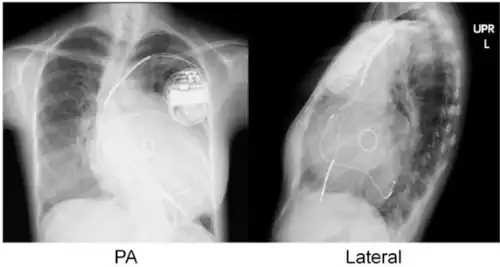

Cardiac resynchronisation therapy (CRT or CRT-P) is the insertion of electrodes in the left and right ventricles of the heart, as well as on occasion the right atrium, to treat heart failure by coordinating the function of the left and right ventricles via a pacemaker, a small device inserted into the anterior chest wall.[1]

The insertion of electrodes into the ventricles is done under local anesthetic, with access to the ventricles most commonly via the subclavian vein, although access may be conferred from the axillary or cephalic veins. Right ventricular access is direct, while left ventricular access is conferred via the coronary sinus (CS).

- Atrial lead at the right appendage

- Right ventricular lead at the apex

- Left ventricular lead through the coronary sinus.[7]

CRT requires the placement of an electrical device for biventricular pacing, along with placement of (at least) two pacing leads, to facilitate stable left ventricular and right ventricular pacing. For all elements, the first stage of the process is local anaesthetic followed by incision to allow for approach from the appropriate vein. From here, the leads and device can be inserted.[1]

Device placement

The device is inserted in a subcutaneous pocket created by the surgeon, the choice of left or right side of the chest wall is determined mainly by the patient's preference or location of preexisting device. The device, similar to that of a traditional pacemaker, is generally no larger than a pocket watch and has inserts for the electrode leads.[1]